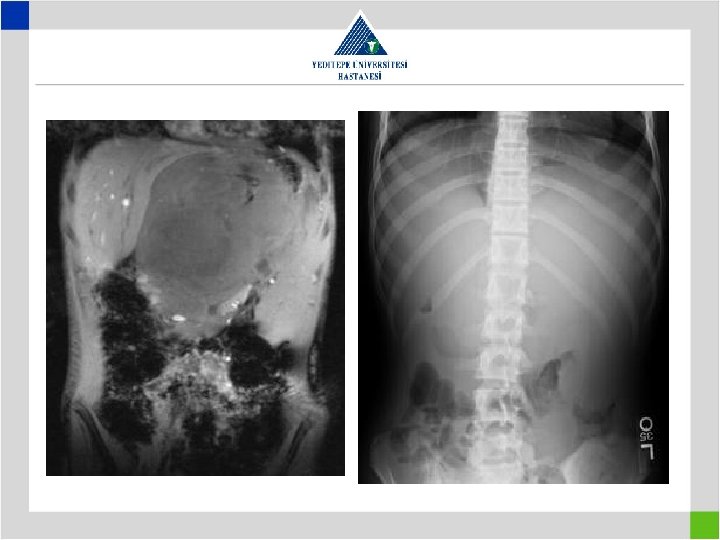

• Fetal MRI